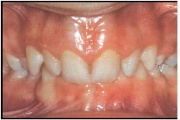

Turritavad ülemised lõikehambad.

Normaalse jäävhammaskonna pilt küljelt ja eest vaadatuna.